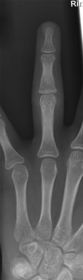

| Oblique Digit | finger not parallel to IR *should be more concave to one side* |

| Oblique Digit | finger not obliqued to 45 degrees - can't see the concavity of one side of the digit joint spaces closed |

| Lateral Digit | finger bent back - not truly lateral |

| Lateral Digit | artifact |

| What's the evaluation criteria for the PA Finger X-Ray? | ANATOMY: distal phalynx -> distal 1/2 of metacarpal demonstrated CRITERIA: - equal concavity on both sides of phalanges - IP and MCP open - no overlapping of adjacent fingers POSITIONING: CR perpendicular @ PIP joint |

| What's the evaluation criteria for the Lateral finger x-ray? | ANATOMY: entire digit demonstrated CRITERIA: open joint spaces concave to one side, while the dorsal side is straight no overlapping of adjacent fingers/soft tissues POSITIONING: CR perpendicular @ PIP joint |

| Oblique finger x-ray image criteria? | ANATOMY: entire digit demonstrated CRITERIA: more concavity to one side open joint spaces no superimposition of adjacent fingers POSITIONING: CR perpendicular @ PIP joint |